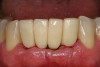

A 53-year-old male presented with localized advanced periodontal disease of the mandibular incisors. Teeth Nos. 23 to 26 exhibited Class II mobility because of advanced bone loss (Figure 1). The teeth had migrated out of position over the years, and a diastema had developed between No. 24 and No. 25 (Figure 2). The patient complained about the poor esthetic appearance of these teeth, and he was able to perceive their loss of strength on function as a result of their mobility.